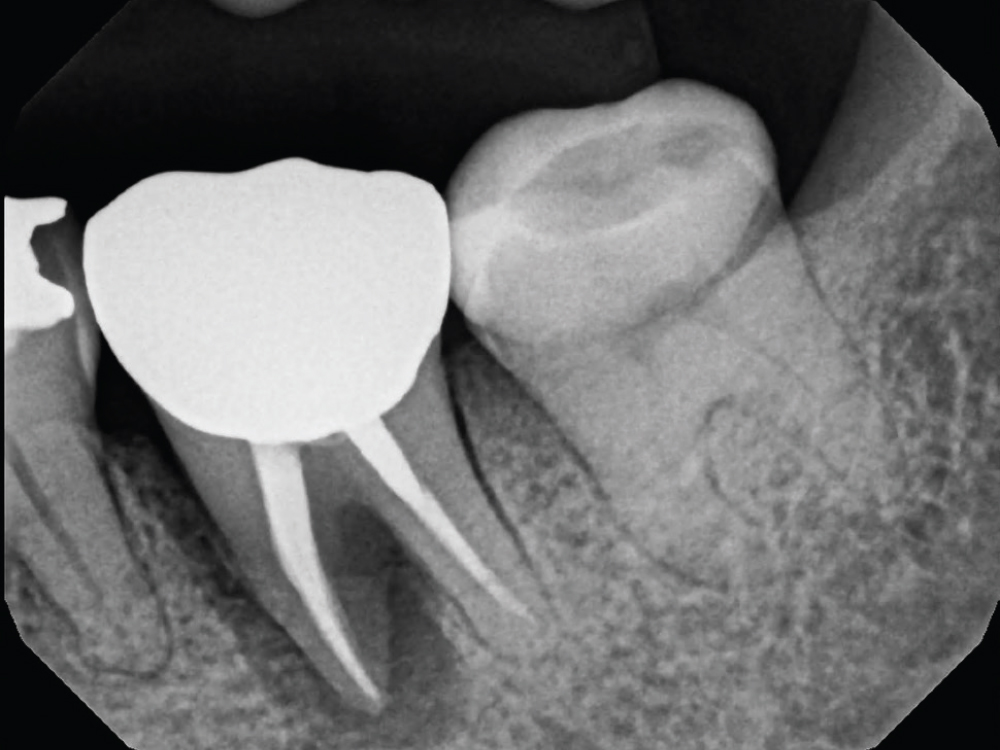

Radiograph of tooth

Figure 2: A radiograph of the tooth confirmed the failing root canal. Because of the significant radiolucency around the furcation and mesial root, we decided the best option was extraction and grafting to establish a good foundation for future implant treatment.